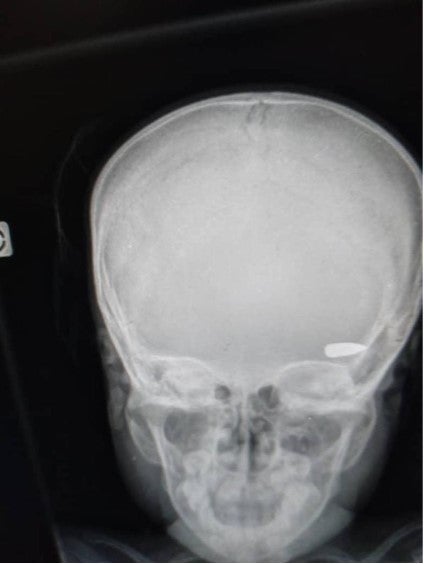

An x-ray image shows a bullet lodged in the head of a child who was hit during a confrontation between criminal groups in the Brooklyn neighborhood of Cité Soleil commune in early April 2023

© 2023 Private